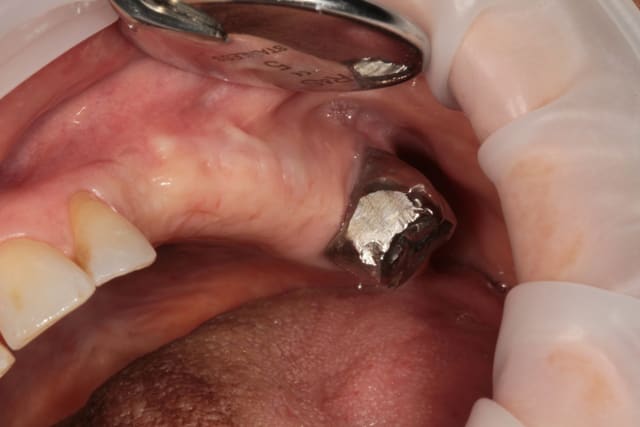

Bonjour mes CHERS AMIS, ouverture à 5 mois, et comme vous êtes sympas, je fais un lambeau (la patiente me pardonnera)

deux trois photos pour montrer que crédulité et optimise ne vont pas de pair....

ah ! oui, le VITAL OS à super bien fonctionné ici.

mais Xavier y est certainement pour quelque chose...

c'est bien mené, on voit nettement la différence entre l'avant et l'après, surtout le volume des crêtes.

top!